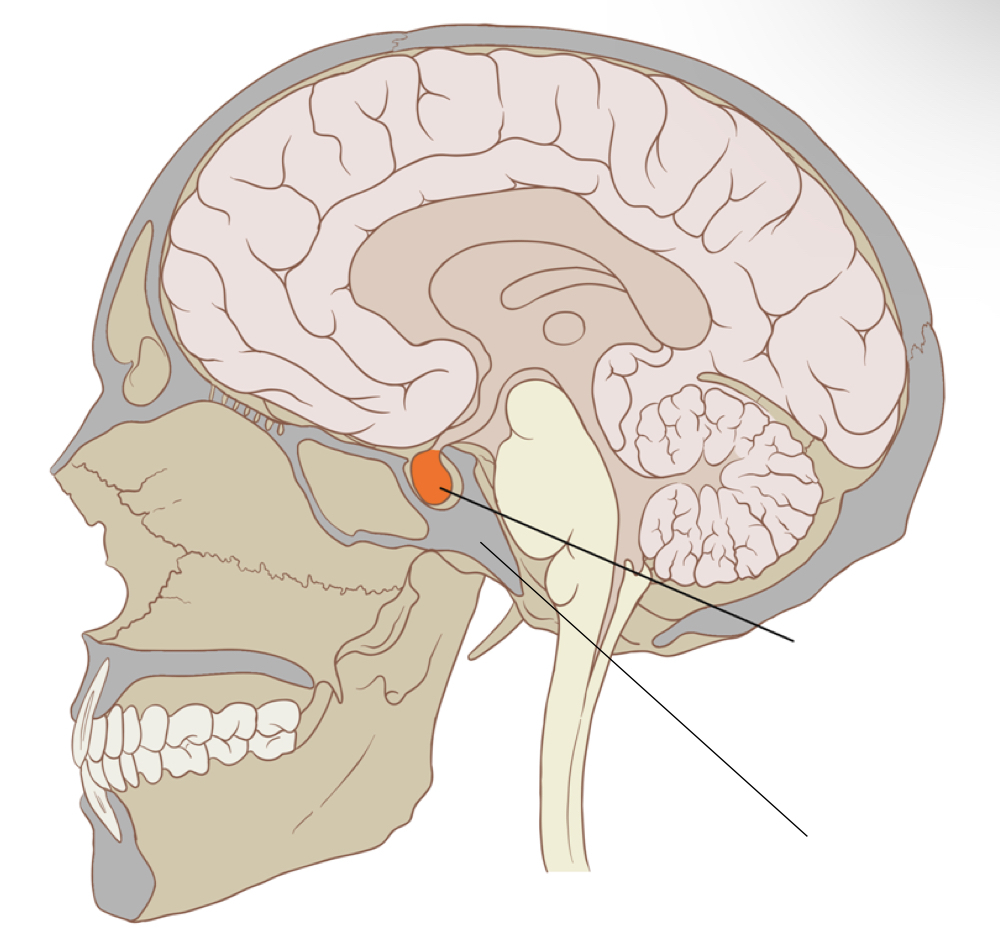

Sella Turcica

The sella turcica is a deep ___ on the ___ surface of the ___ bone of the skull. It houses and protects the ___ gland, which is an ___ gland that controls many of the ___ within our bodies.

The sella turcica lies in the midsagittal plane of the ___ at a point ¾ inch ___ and ¾ inch ___ to the ___.

The sella turcica is a deep depression on the superior surface of the sphenoid bone of the skull. It houses and protects the pituitary gland, which is an endocrine gland that controls many of the hormones within our bodies.

The sella turcica lies in the midsagittal plane of the cranium at a point ¾ inch anterior and ¾ inch superior to the EAM.

Sella Turcica Anatomy